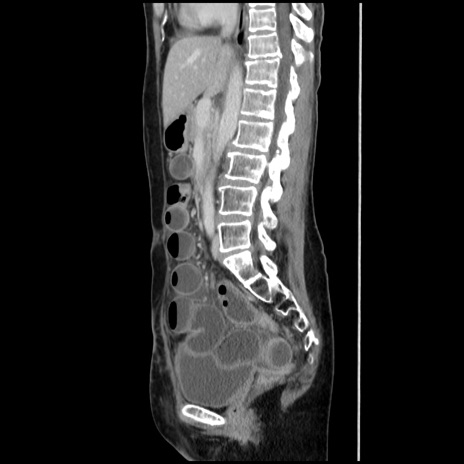

症例32(矢状断像)

【症例】40歳代 女性

【主訴】上腹部痛、嘔気・嘔吐

【現病歴】約9時間前頃から急に上腹部痛、嘔気、嘔吐が出現。改善しないため救急要請。

【既往歴】子宮頚癌(広汎子宮全摘術、放射線療法)、腸閉塞

【身体所見】腹部:平坦、軟、腸雑音亢進、上腹部を中心に腹部全体に圧痛あり。

【データ】WBC 8400、CRP 0.03

横断像